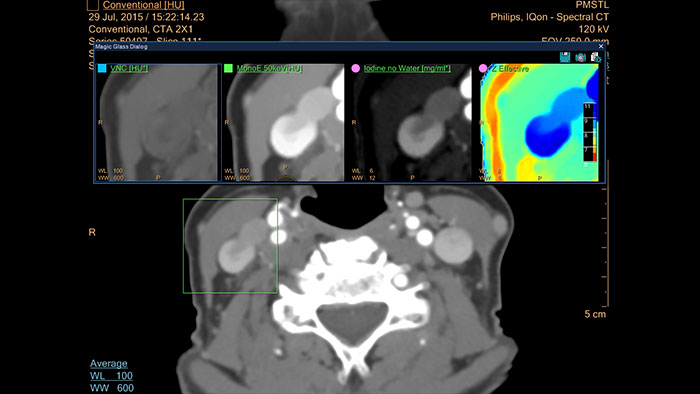

- Spectral Advanced Vessel Analysis

-

CT Spectral Advanced Vessel Analysis

IQon Spectral CT Functionality

Benefits

- Bone removal on different energy levels.

- Spectral plots to characterize plaque and stenosis.

- Different energy results comparison.

- Evaluation of the extent of lumen occlusion.

- Spectral Comprehensive Cardiac Analysis

-

CT Spectral Comprehensive Cardiac Analysis

IQon Spectral CT Functionality

Provides the ability to run cardiac segmentation on different energy levels, compare vessel curves with various spectral data types, and enhance the visual assessment of coronary vessel patency.

Benefits

- Automatic chamber and coronary segmentation using mono-energetic images.

- Beam hardening reduction for: perfusion deficits visualization and calcified plaque visualization.